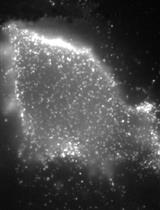

TRIPLE (Insulin, Glucagon and EGFP) Immunofluorescence Staining Protocol in Pancreas

胰腺的三重(胰岛素、胰高血糖素和增强型绿色荧光蛋白(EGFP))免疫荧光染色法